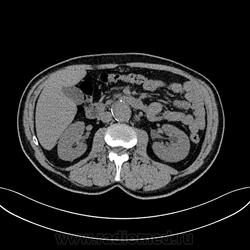

Пациент лежит в кардиологии. Прислали на аортографию. 2 врача УЗИ несколько разошлись в диагнозах: одна видит тромбированную аневризму брюшной аорты, другая - тромбоз нижней полой вены.

А мы получили вот такие красивые картинки.

Шикарно! Тромбированная аневризма инфраренального отдела (над бифуркацией), бифуркации и общих подвздошных артерий, синдром Лериша справа.

И еще маленькая аневризмочка наружной подвздошной слева. Честно говоря, меня больше всего впечатлили коллатерали, благодаря которым клинически он вообще не соответствует исследованию. Конечности теплые, пульсация слабая, но как-то прослеживается...